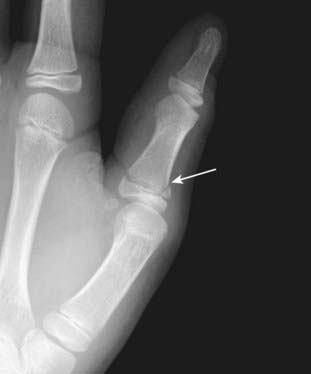

image Boxer’s fracture is a fracture of the head of the 5th metacarpal (little finger) with palmar angulation of the distal fracture fragment. It is most often the result of punching a person or wall (Fig. 22-24).

Figure 22-24 Boxer’s fracture.

A boxer’s fracture is a fracture of the head of the 5th metacarpal with palmar angulation of the distal fracture fragment (solid black arrow). It is most often the result of punching a person (or a wall).